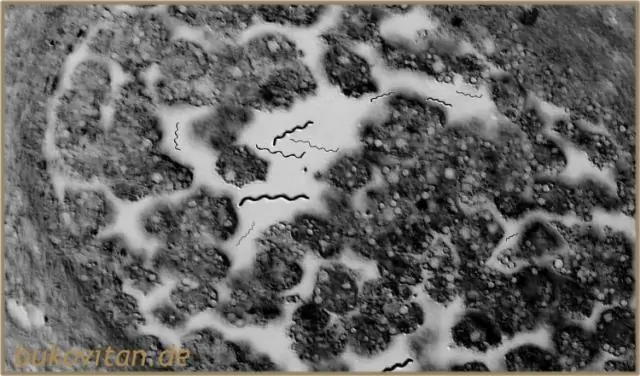

СПОСОБ ПЕРЕДАЧИ: Заболевание обычно передается через укус инфекционного комара. Всего существует 6 родов и 70 видов комаров, ответственных за распространение Wuchereria Bancrofti (1).

Эти нитчатые черви распространяются различными видами комаров-переносчиков. W. Bancrofti является наиболее распространенным из трех и затрагивает более 120 миллионов человек, в основном в Центральной Африке и дельте Нила, в Южной и Центральной Америке, тропических регионах Азии, включая южный Китай, и на островах Тихого океана.